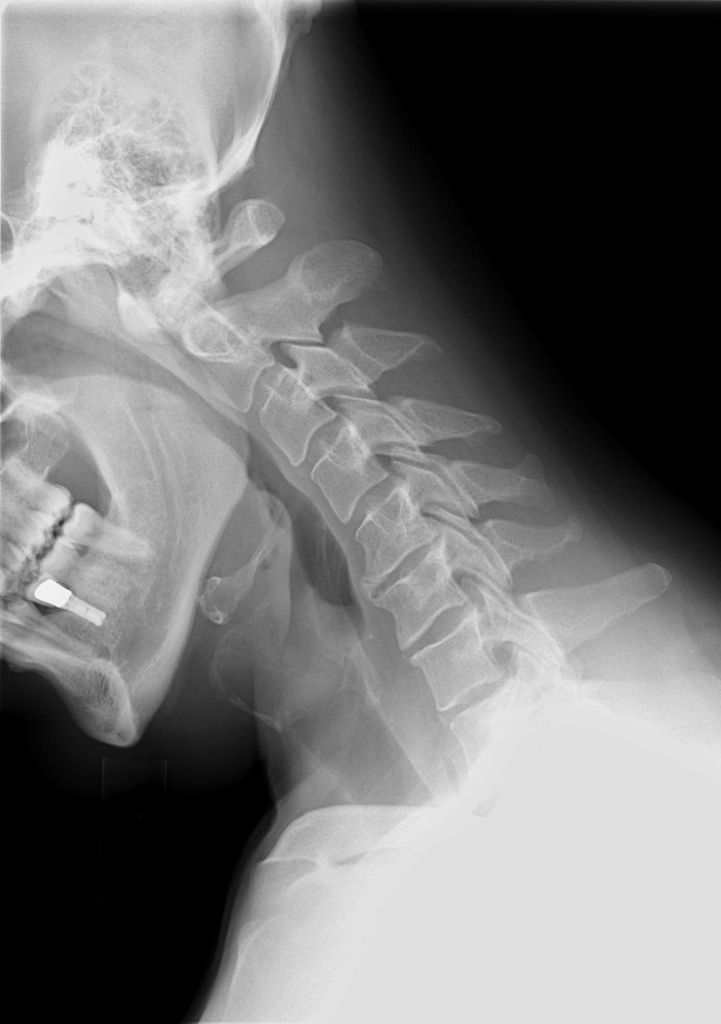

X-rays

It provides a clear image of the dense internal structure like bones. So, the x-ray taken in the neck region shows the bone alignment along the neck. The images also reveal any degenerative changes occurring in the cervical spine. So, your doctor can uncover problems like the presence of bone spurs or disk height loss with the x-ray images.